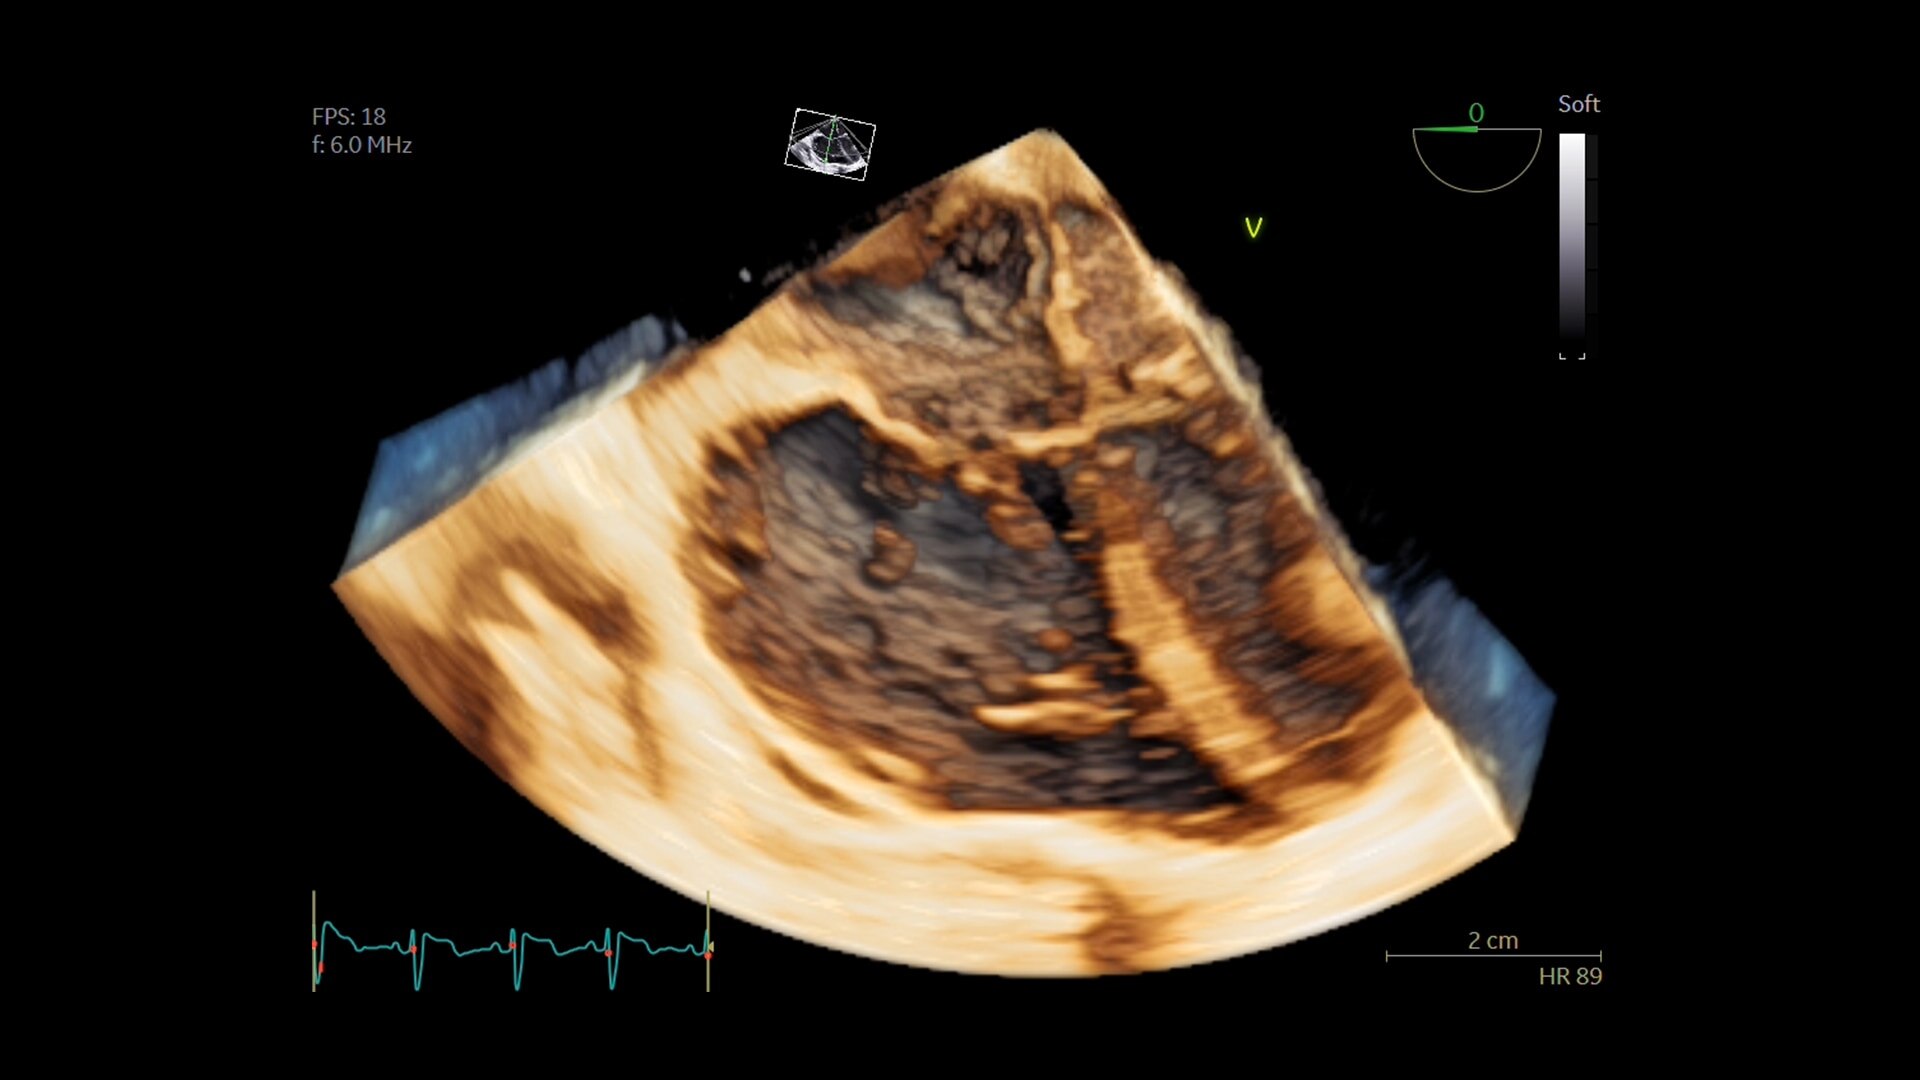

В видеоролике представлен практический опыт внедрения технологии Air Recon DL (ARDL) — технологии реконструкции МР-изображений на основе алгоритмов глубокого обучения. В отличие от традиционных методов постобработки ARDL позволяет значительно снизить уровень шума, повысить пространственное разрешение и четкость изображений без увеличения времени сканирования.